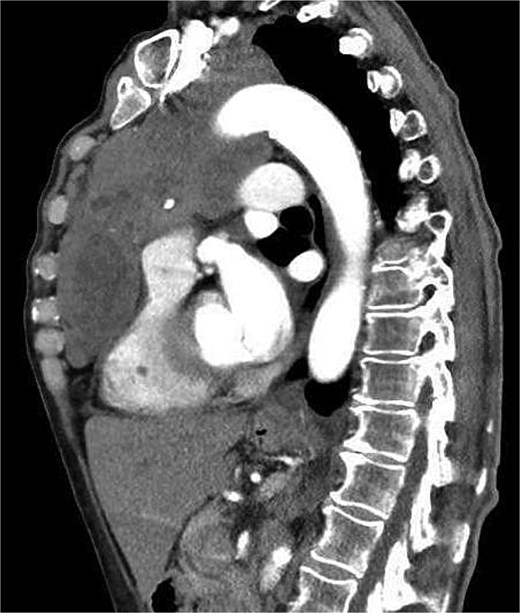

A 71-year-old female presented to her general practitioner with unintentional weight loss of 30 kg over the course of 6 months. She denied any further complaints. Her medical history included arterial hypertension and type II diabetes mellitus with no previous oncological history. Clinical examination revealed a cachectic patient without other relevant findings. A chest X-ray was performed as the initial imaging study, which showed an enlarged mediastinum (Fig. 1). In the case of a suspected mediastinal tumor, a chest CT scan was conducted and confirmed the presence of a 11.4 × 9.2 cm mediastinal tumor in the anterior mediastinum (Fig. 2). CT imaging revealed, in addition to the infiltration of the chest wall, a very close relationship with the aortic arch and the left subclavian artery. Further evaluation took place at a local hospital. First, an endobronchial ultrasound with transbronchial needle aspiration (EBUS-TBNA) of left paratracheal tumor mass revealed a B2 thymoma. Staging was completed with magnetic resonance tomography (MRI) of the brain, which excluded cerebral metastases. Due to suspicion of infiltration of the aorta, a complementary MRI of the mediastinum was performed but provided no additional information. The case was presented at a multidisciplinary tumor board in the presence of thoracic surgeons. The tumor was deemed inoperable and treated with four cycles of carboplatin and paclitaxel. At restaging, definitive radiotherapy was recommended. The patient sought a second opinion in our department. Re-staging with CT showed stable disease. The tumor was suspected to invade the sternum, left 1st to 3rd ribs, pericardium, and left upper lobe. Infiltration of the aorta appeared unlikely but could not be completely excluded.

Chest CT in sagittal view showing a large tumor mass in the anterior mediastinum.